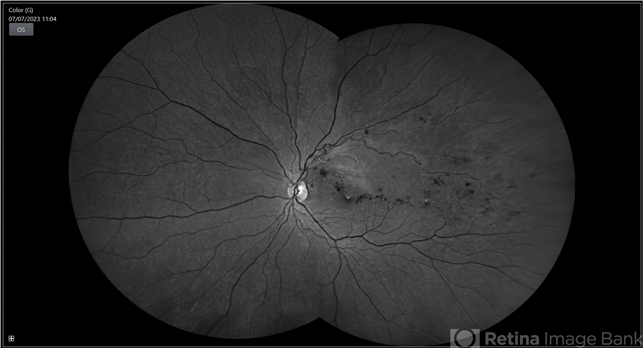

Branch retinal vein occlusion - Colour & Red free image - ring shaped collaterals

BRVO, branch retinal vein occlusion (BRVO), non-perfused branch retinal vein occlusion (BRVO)

43-year-old woman presented with left eye old STBRVO with chronic CME of duration 6month showing ring shaped collaterals more evident on red free image